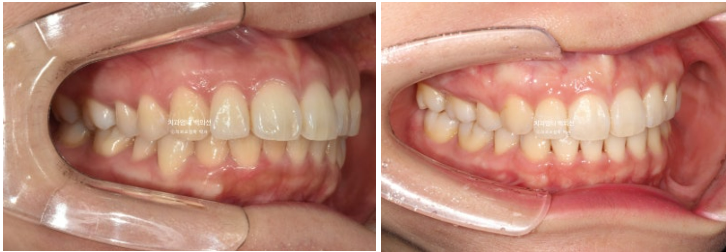

22.09~25.04

이제 돌출입 발치교정 입술부전증 치료 후 안모 비교 보겠습니다.

정돈된 스마일라인과 입동굴이 매력적입니다.

치료계획을 변경한 덕에 중간평가 이후 입매가 너무 들어가지 않고 적정선에서 마무리가 잘 되었습니다.